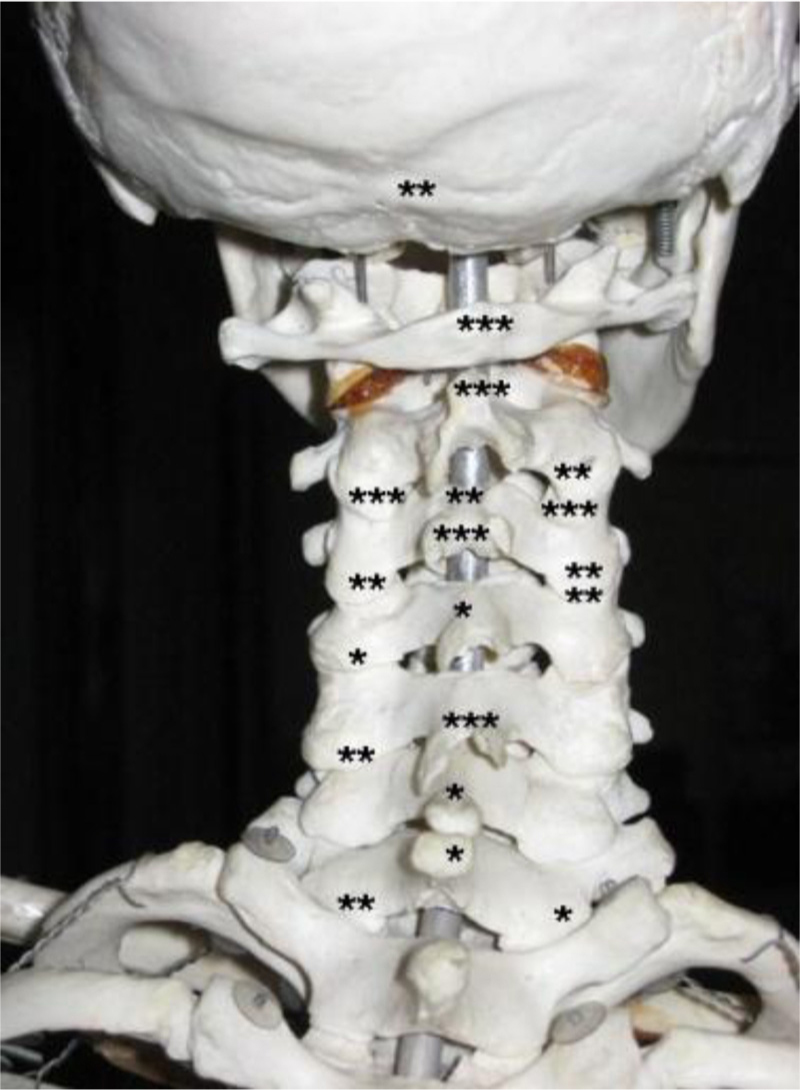

Distribution of high blood flow in 20 controls. Each dot represents the localization of high blood flow found in a region in a single control (regardless of intensity).